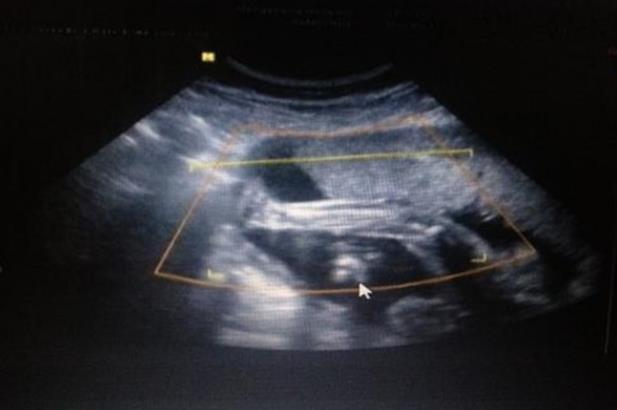

IVF是體外受精-胚胎移植的簡(jiǎn)稱。具體過(guò)程是把女方的卵子和男方的精子取出體外。經(jīng)過(guò)優(yōu)化處理后,在體外完成受精,將胚胎放回女性子宮。對(duì)于想做試管嬰兒的夫婦來(lái)說(shuō),首先要在初診時(shí)明確做試管嬰兒的指征,自身情況是否適合做試管嬰兒。另外,你還要準(zhǔn)備好夫妻雙方的身份證和結(jié)婚證備案。報(bào)告出來(lái)后,生殖專家會(huì)根據(jù)檢查結(jié)果和患者的實(shí)際情況制定促排卵方案,然后根據(jù)擬定的方案和女方的月經(jīng)周期安排后續(xù)的就醫(yī)時(shí)間。